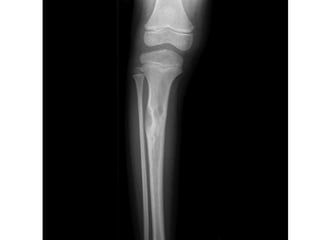

OSTEOFIBROUS DYSPLASIA

• Osteofibrous dysplasia (OFD) is a benign, non-osseous

the tibia, particularly in children or teenagers.

can on rare occasions be polyostotic.

occasion affect the ipsilateral fibula or be bilateral at

• It presents with moderate expansion of bone which is

the tibia.

pathological fractures can occur.

• The lesion classically presents radiographically as

intracortical osteolysis, most commonly affecting the

• There is expansion of the cortex to accommodate the lesion

• There is a narrow zone of transition between the lesion and

the medullary side, which may obscure the medullary

• MRI demonstrates a cortical lesion with a surrounding area

comparable malignant variant, adamantinoma, which

medullary involvement.